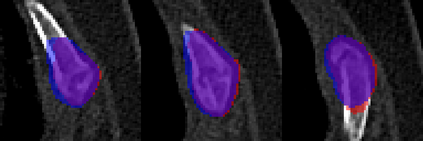

Rib fractures are a common and potentially severe injury that can be challenging and labor-intensive to detect in CT scans. While there have been efforts to address this field, the lack of large-scale annotated datasets and evaluation benchmarks has hindered the development and validation of deep learning algorithms. To address this issue, the RibFrac Challenge was introduced, providing a benchmark dataset of over 5,000 rib fractures from 660 CT scans, with voxel-level instance mask annotations and diagnosis labels for four clinical categories (buckle, nondisplaced, displaced, or segmental). The challenge includes two tracks: a detection (instance segmentation) track evaluated by an FROC-style metric and a classification track evaluated by an F1-style metric. During the MICCAI 2020 challenge period, 243 results were evaluated, and seven teams were invited to participate in the challenge summary. The analysis revealed that several top rib fracture detection solutions achieved performance comparable or even better than human experts. Nevertheless, the current rib fracture classification solutions are hardly clinically applicable, which can be an interesting area in the future. As an active benchmark and research resource, the data and online evaluation of the RibFrac Challenge are available at the challenge website. As an independent contribution, we have also extended our previous internal baseline by incorporating recent advancements in large-scale pretrained networks and point-based rib segmentation techniques. The resulting FracNet+ demonstrates competitive performance in rib fracture detection, which lays a foundation for further research and development in AI-assisted rib fracture detection and diagnosis.